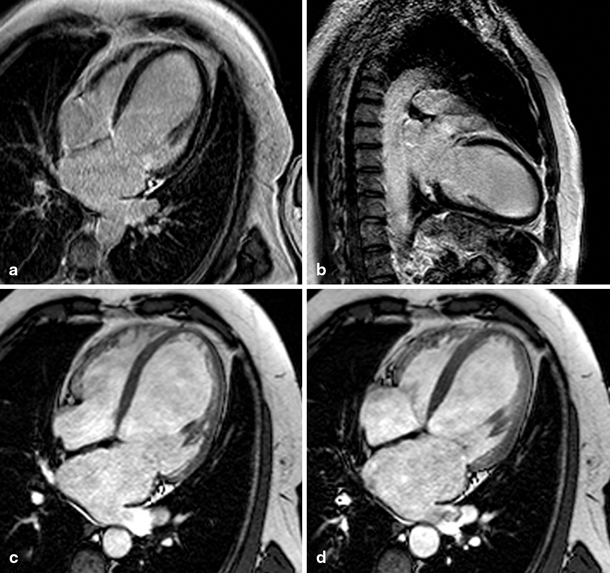

The RVEF was more impaired and RV size larger in patients with DCM in comparison with patients with IHD (Figs. 3 and 4) despite similar LV systolic and diastolic dysfunction. There was an isolated increase in E/e’ of the septum in DCM patients, but an opposite trend laterally and no further differences were seen in diastolic parameters between the groups, suggesting no difference in diastolic LV function. LV EDV and ESV were not different between the groups. All CMR and echocardiography parameters are summarised in Table 1.

Fig. 3

Late gadolinium enhancement (a, b) and cine (four-chamber view in end-diastole (c) and end-systole (d)) magnetic resonance images of a patient with idiopathic dilated cardiomyopathy (left ventricular ejection fraction 24 %, right ventricular ejection fraction 45 %) The left ventricular systolic function of this patient is slightly better than that of the patients with ischaemic heart disease from Figs. 1 and 2 while the right ventricular function is more impaired. Areas of late enhancement are not present